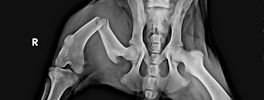

Images

Digital X-Ray